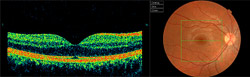

With the help of the latest technology in ophthalmological exploration, we are able to detect retinopathies in the earliest stages of macular degeneration, when the patient may not report any kind of symptoms. This is the case with Optical Coherence Tomography (OCT).

This technique examines retinal layers through images, visualizing a cross-section of the desired area of the retina. The slightest irregularity among the layers (as in cases of AMD) is projected, measured, compared and monitored, thanks to the different visual perspectives offered by the software. Even 3-D imaging of the retina can be obtained.

A database of population studies is incorporated, giving us automatic comparisons of the thickness of retinal ganglion fibers which lead to the optic nerve, and in this way assess their normality. This is especially useful in the case of patients with glaucoma, both as a support to diagnosis as well as in monitoring its development over time.